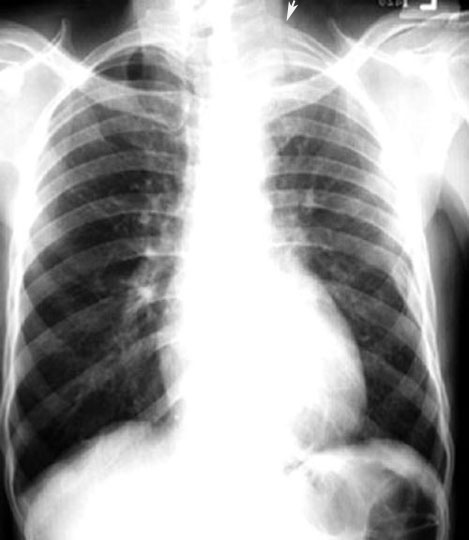

Apical Mass with rib destruction

O'Connell, et. al., in their study of 29 patients with pancoast tumor noted an apical mass to be apparent in 45% of the chest radiographs.